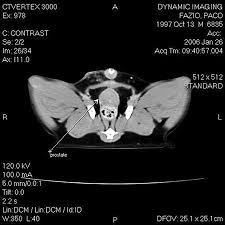

You'll likely hear heavy breathing and shortness of breath. Is bladder cancer painful for dogs? Acvim cancer of the urinary tract in dogs can affect the kidneys, ureters, urinary bladder, prostate, or urethra (see figure 1). Radiation and pain medication are the typical modes of treatment for these stages. Urinary bladder cancer, also called rhabdomyosarcoma, is a type of cancer found in the muscle walls of the bladder or the trigone.